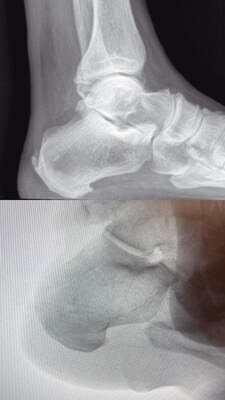

NEWPORT NEWS, Va., Nov. 12, 2024 /PRNewswire/ — Bryanna D. Vesely, DPM, MPH, performed the first minimally invasive Haglund’s repair surgery on the Virginia Peninsula using the Arthrex MIS FiberTak Achilles SpeedBridge Implant Repair System. The surgery was performed Monday, November 11 at Mercy Bon Secours Mary Immaculate Hospital in Newport News, Virginia.

This outpatient procedure was performed on a 68-year-old male patient who had a history of chronic Haglund’s Syndrome. The patient had received multiple prior treatments, including a rigorous stretching program, oral and topical anti-inflammatory medication, shoe modifications, and immobilization, which were unsuccessful in symptom resolution. The patient tolerated the procedure very well and was released to go home after 2 hours of recovery.